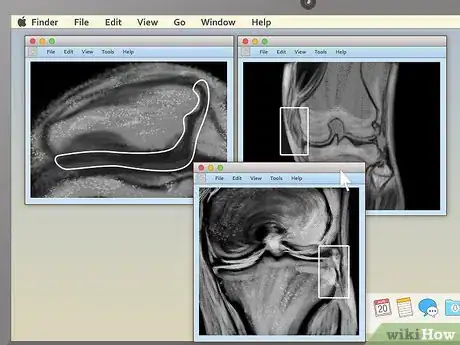

3Pick an appealing series layout. MRI programs almost always have the ability to display more than one image at once. This makes it convenient for doctors to compare different views of the same area or even MRIs taken at different times. For most non-doctors, it's easiest to simply choose a one-image-at-a-time layout and cycle through the images individually. However, there should be onscreen instructions to show two, four, or many more images at once, so feel free to play around with this feature.

4Use the section-cut line to see where cross-sections are located. If you display a cross-sectional image along with a sagittal or coronal image, you may see a section-cut line on the second image. This will be a straight line running through the image, but it may not be present on all MRIs. If your image does have one, this shows where on the second image the cross section is located. You should be able to move the section cut line toward the center, right or left of the image. This will change the larger layout image to show the body from the new direction of the scan.

- The section-cut line on the layout picture also shows the direction that the image was taken from. For example, if your MRI were a picture of an everyday object, like a tree, the section cut line might show you if the picture was taken from above in a plane, from a second-story window, or from the ground.

-

5Drag the section-cut line to view new parts of the study. Dragging the section-cut line to a different part of the image allows you to "move around" your MRI images. The image should change your view to the new area automatically.

- For example, if you're viewing a sagittal image of your spine along with a cross section of one of your vertebrae, moving the section-cut line may allow you to cycle up and down through the various vertebrae above and below it. This can be useful for locating problems like herniated discs.